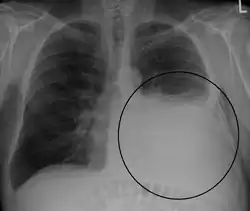

A pleural effusion appears as an area of whiteness on a standard posteroanterior chest X-ray.[15] Normally, the space between the visceral pleura and the parietal pleura cannot be seen. A pleural effusion infiltrates the space between these layers. Because the pleural effusion has a density similar to water, it can be seen on radiographs. Since the effusion has greater density than the rest of the lung, it gravitates towards the lower portions of the pleural cavity. The pleural effusion behaves according to basic fluid dynamics, conforming to the shape of pleural space, which is determined by the lung and chest wall. If the pleural space contains both air and fluid, then an air-fluid level that is horizontal will be present, instead of conforming to the lung space.[16] Chest radiographs in the lateral decubitus position (with the patient lying on the side of the pleural effusion) are more sensitive and can detect as little as 50 mL of fluid. Between 250 and 600mL of fluid must be present before upright chest X-rays can detect a pleural effusion (e.g., blunted costophrenic angles).[17]

Massive left-sided pleural effusion (whiteness) in a patient presenting with lung cancer. -

Massive pleural effusion, later proven to be hemothorax in a South Indian male.